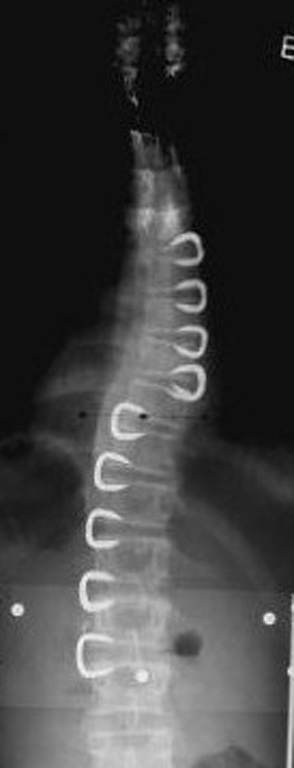

Grafilerle Skolyoz